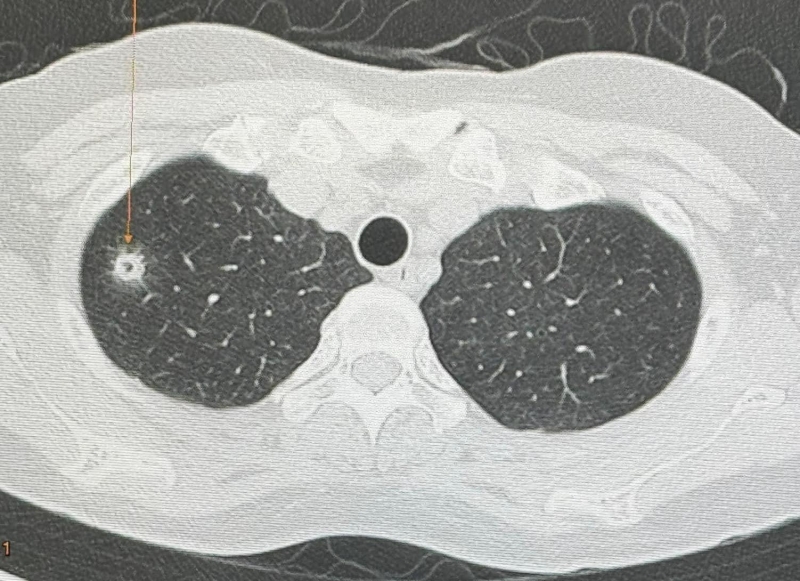

นพ.มนูญ ลีเชวงวงศ์ แพทย์เฉพาะทางด้านโรคระบบการหายใจ รพ.วิชัยยุทธ โพสต์ ผู้ป่วยหญิงอายุ 52 ปี บ้านอยู่ กทม. ปกติแข็งแรงดี ไม่ไอ ไม่มีไข้ ไม่เบื่ออาหาร น้ำหนักไม่ลด ไม่ปวดหัว ไม่เคยสูบบุหรี่ ไม่มีโรคประจำตัว ไปตรวจร่างกายประจำปี วันที่ 12 พฤษภาคม 2567 เอกซเรย์ปอด พบก้อนเล็กๆ เกิดขึ้นใหม่ที่ปอดขวากลีบบน (ดูรูป) เอกซเรย์ปอดก่อนหน้านั้น 1 ปีปกติ ทำคอมพิวเตอร์ปอดพบก้อนขนาด 0.9 × 0.9 × 1.7 เซนติเมตร เห็นโพรงอยู่ข้างในก้อนที่ปอดขวากลีบบน (ดูรูป) ตรวจเลือดไม่ติดเชื้อเอชไอวี